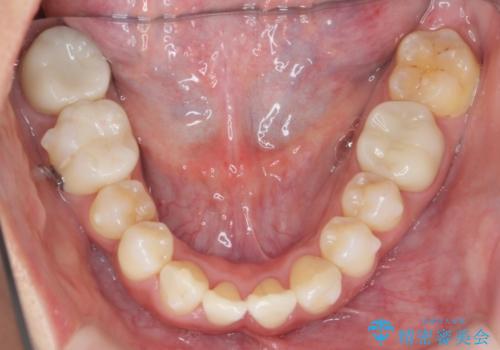

職業柄ワイヤー矯正ができない、マウスピース矯正で行う八重歯抜歯症例

治療に制約がある場合でも、現実的な治療ゴールを設定することで機能的・審美的な歯並びを手に入れることができました。